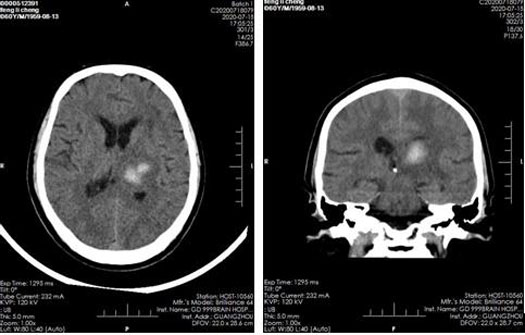

影像检查:

2020年7月18日CT结果显示:左侧丘脑-基底节脑出血并水肿;幕上轻度脑萎缩。